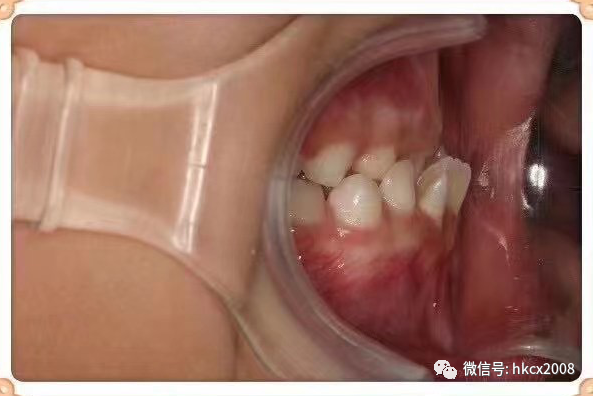

图片

矫治前